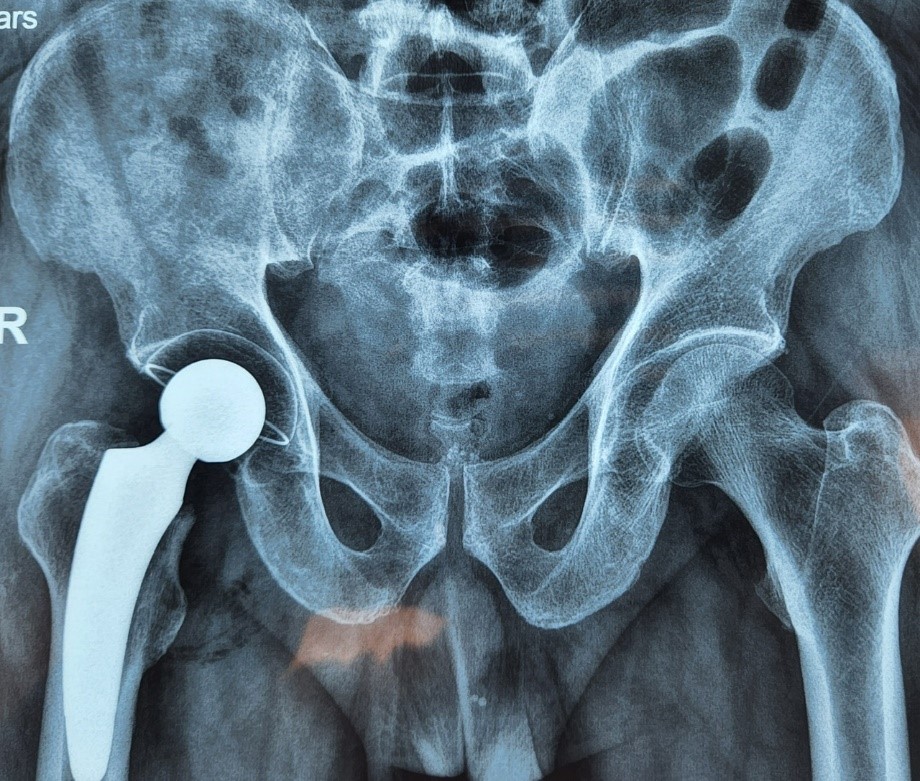

Ổ cối đã được cốt hóa thành một phần xương chậu – Hình: Trung tâm CTCH

Tại trung tâm Chấn thương chỉnh hình và Cột sống Hoàn Mỹ, bệnh viện Hoàn Mỹ Sài Gòn, sản phẩm được sử dụng là khớp háng toàn phần không xi măng với chuôi Optimys và ổ cối RM Pressfit từ Thụy Sĩ. Các thiết bị này hỗ trợ xương phát triển bám vào ổ cối, biến ổ cối thành một phần của xương chậu, từ đó kéo dài tuổi thọ của khớp.